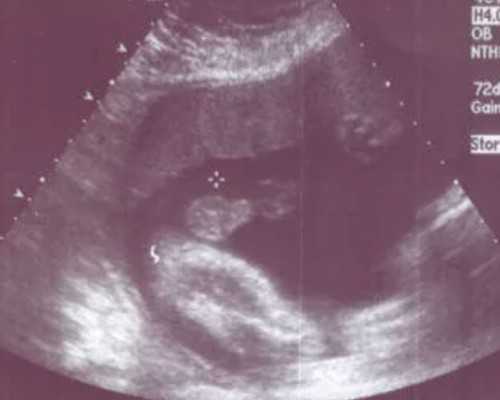

内膜准备和监测也对试管移植的成功起着至关重要的作用。医生会通过超声波检查和血液检测来确保内膜厚度和质量符合移植要求。